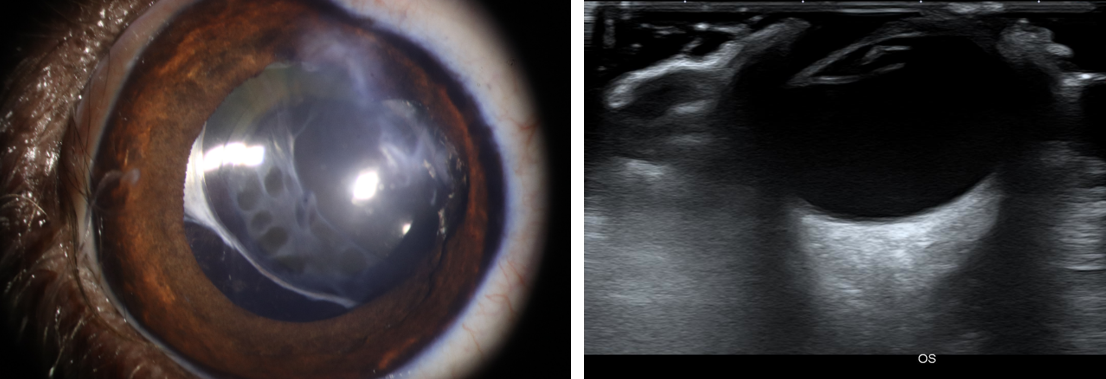

사진4. 이전 시력 소실, 안압 상승 확인되었으나 수술적 교정 후 이상 증상 없음. 수술 후 5개월 세극등 현미경 사진 (좌). 초음파 검사상 후안부 등 안구 조물에 이상 확인되지 않음 (우).